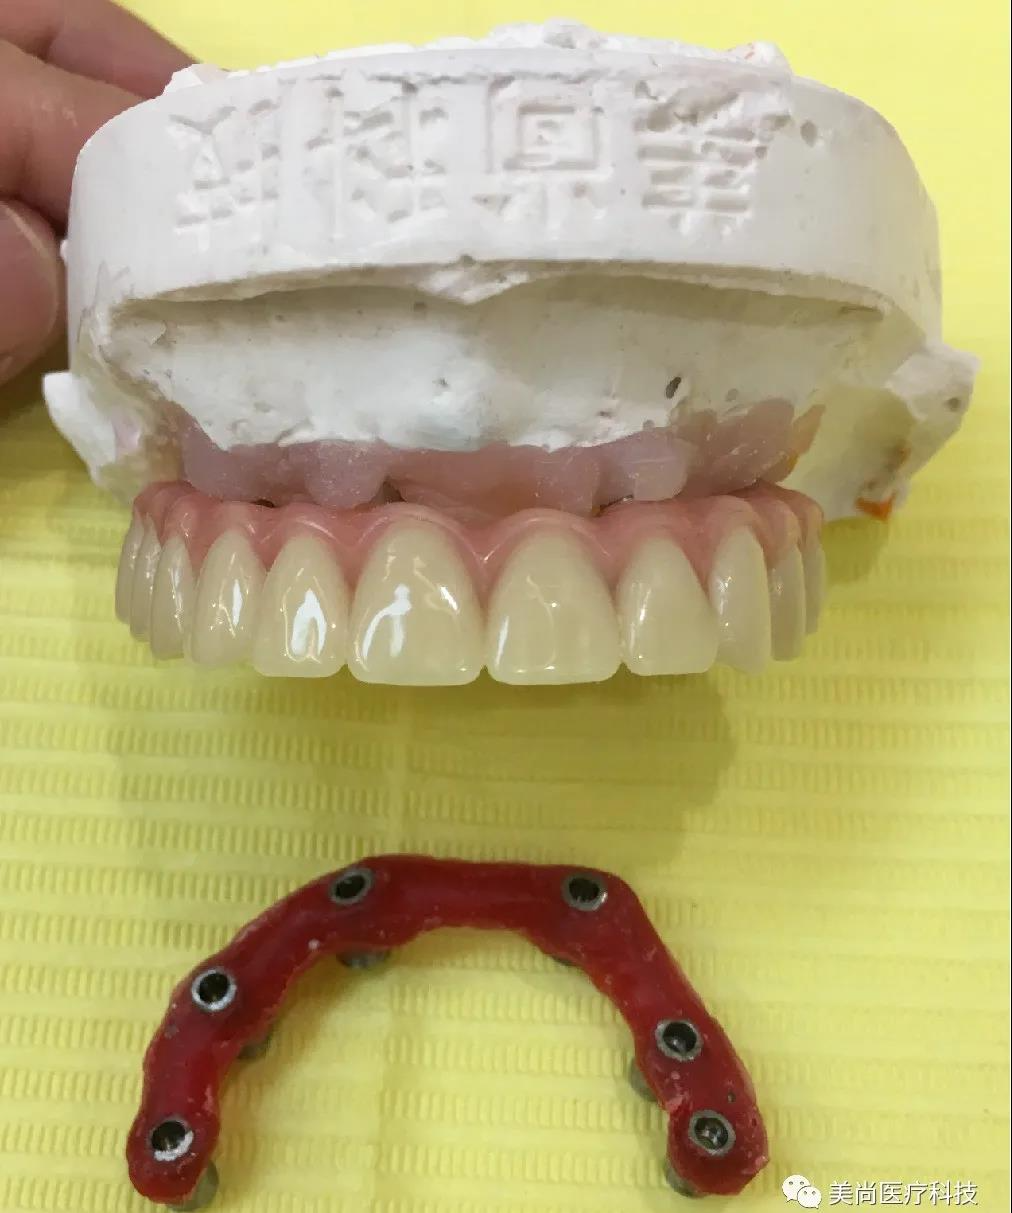

制作种植导板